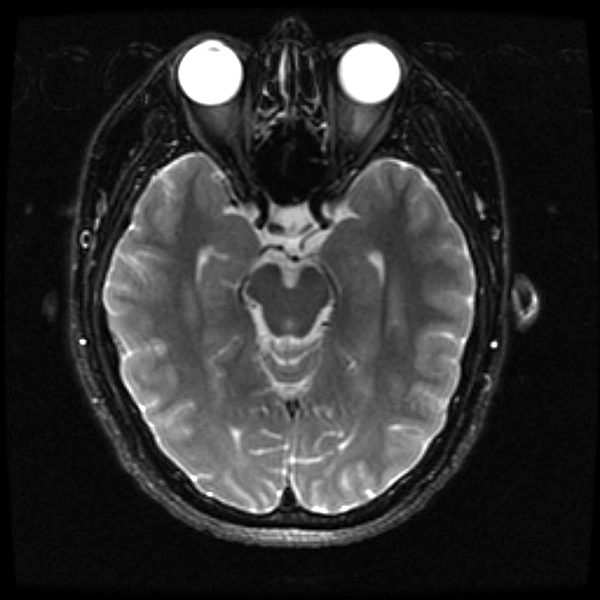

once i got back home and checked out my scans in osirix (the mac os x application to view DICOM medical imaging slides), i was blown away. talk about invasive: you haven't seen intimate until you've looked at photos of the inside of your body. the coolest part is since the scans were done in cross-sections, i can animate the scans so it looks like the beam is passing through my neck and head (all 800+ images). i've always known that inside my body was all sorts of muscles and veins and organs, but i guess i was hoping for something less messy, maybe circuit boards and memory chips instead. i know MRI's were first used in the late 60's, but this is my first time experiencing the technology in-person and it's pretty amazing. talk about futuristic! to be able to see with so much detail the insides of my body without having to cut me open! if scientists can do this, what else can they do? my only regret is they only imaged me from my shoulder up. i'd love to have a full-body scan. maybe i can fake some sort of internal injury and get my doctor to okay the procedure. i recommend anyone who's never had an MRI done to do so when they have the chance.

speaking of doctors, the main reason why i was at MGH this morning was for a follow-up appointment with my doctor. he basically told me that my MRI scans were fine as well as my blood work (he wrote me a letter a few weeks ago, so i already knew the news). since the pain in my neck had already disappeared,